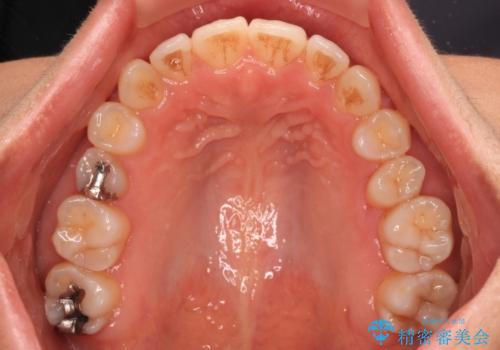

左上奥歯には乳歯が残存しており、後続永久歯は舌側に転位していました。

乳歯を抜歯し、舌側の永久歯を引っ張り出すこととしましたが、希望のインビザラインでは移動量が大きすぎて対応できない可能性があったため、ワイヤー装置にて改善することとしました。

ワイヤー装置にてある程度歯列が改善されたところで、上下をインビザラインにて矯正治療を行うこととしました。